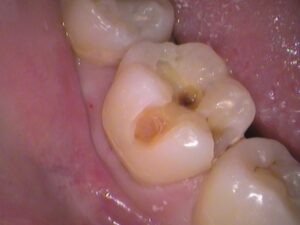

最初にも説明しましたが、

30代女性の方で、検診で虫歯が見つかりました。

本人では分からにくい、

いや、分からない所の虫歯でした。

この場所の虫歯を自分で分かる人はほとんどいません。

場所は、上の奥歯の頬っぺた側に虫歯がありました!

お口の中を見てみると、

すごく黒くなっていますね・・・(*_*)

上の奥歯はご自身では見えませんし、

さらに頬っぺた側は、頬っぺたが邪魔をして自分では見えづらい場所となります。

また歯ブラシも意識して磨かなければ磨けないところです。

汚れが残り、虫歯が徐々に進行していきます。

表面から削っていっている途中ですが、

内部まで黒く虫歯が侵入しています。

左側、頬っぺたがぶつかっている所が黒く虫歯になっており、

内部入り込んでいます。

歯の半分くらい削っています。